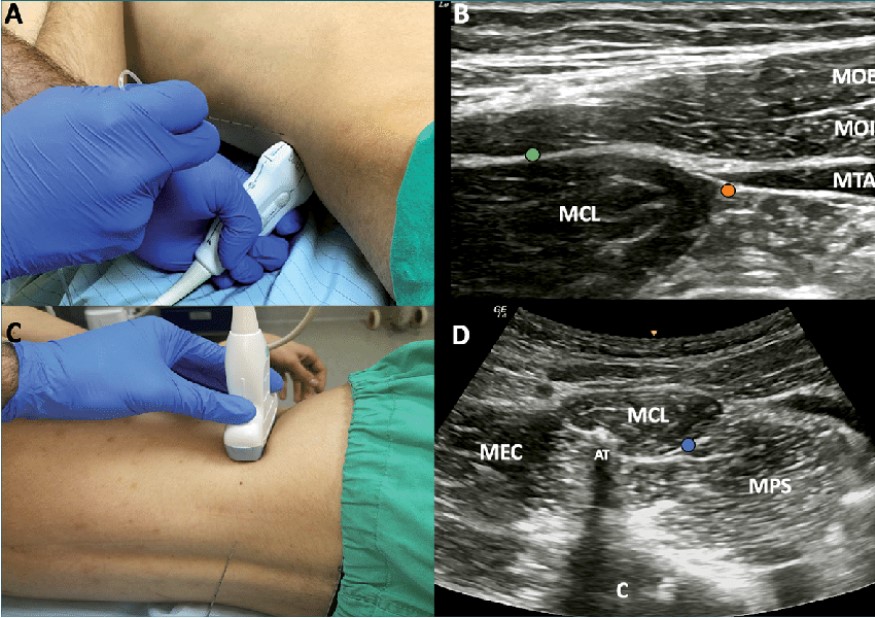

En los casos que nos ocupan, ambos pacientes, varones en la cuarta y quinta décadas de la vida, fueron referidos por un cuadro de dolor abdominal difícil de catalogar, que describían como dolor a punta de dedo, lateral al ombligo, quemante o eléctrico, relacionado con los movimientos y con los esfuerzos (como la maniobra de Valsalva), y que, tras la realización de la maniobra de Carnett y, posteriormente, la ecografía de la pared abdominal, permitieron el diagnóstico.

El signo de Carnett es una maniobra de exploración del dolor abdominal, utilizada para diferenciar el dolor originado en la pared abdominal del dolor de los órganos internos, el dolor visceral. Es positivo si el dolor aumenta o persiste cuando el paciente contrae la musculatura abdominal, al incorporarse del decúbito, mientras se presiona el punto de dolor.

También la realización de una ecografía de la pared abdominal puede detectar anomalías o engrosamientos en la vecindad de las ramas terminales de los nervios intercostales y reforzar la sospecha diagnóstica.

El tratamiento pasa por el bloqueo diagnóstico y terapéutico de los nervios afectados o del plano muscular, empleando anestésico y esteroide y, ocasionalmente reforzado con el empleo de radiofrecuencia pulsada con resultados excelentes y poco agresivo.